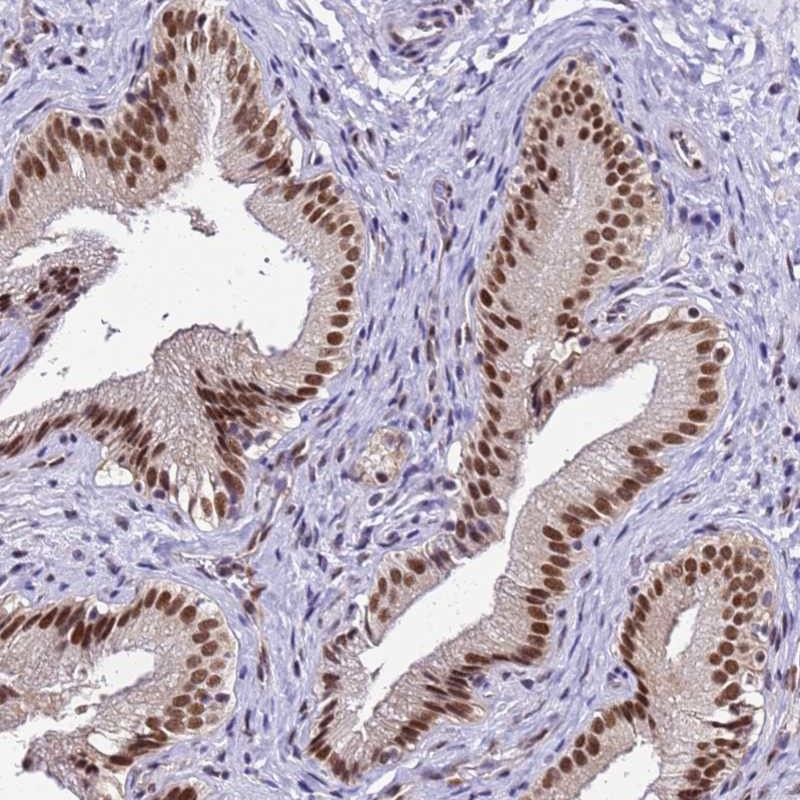

Immunohistochemical staining of human gallbladder shows nuclear positivity in glandular cells.